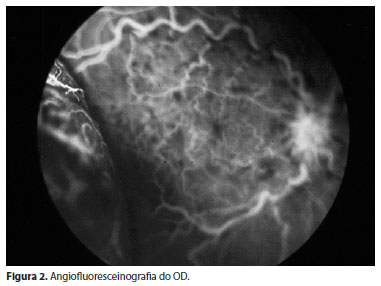

A angiofluoresceinografia (AGF) mostrava o grande comprometimento vascular retiniano e ausência de edema macular (Figura 2).